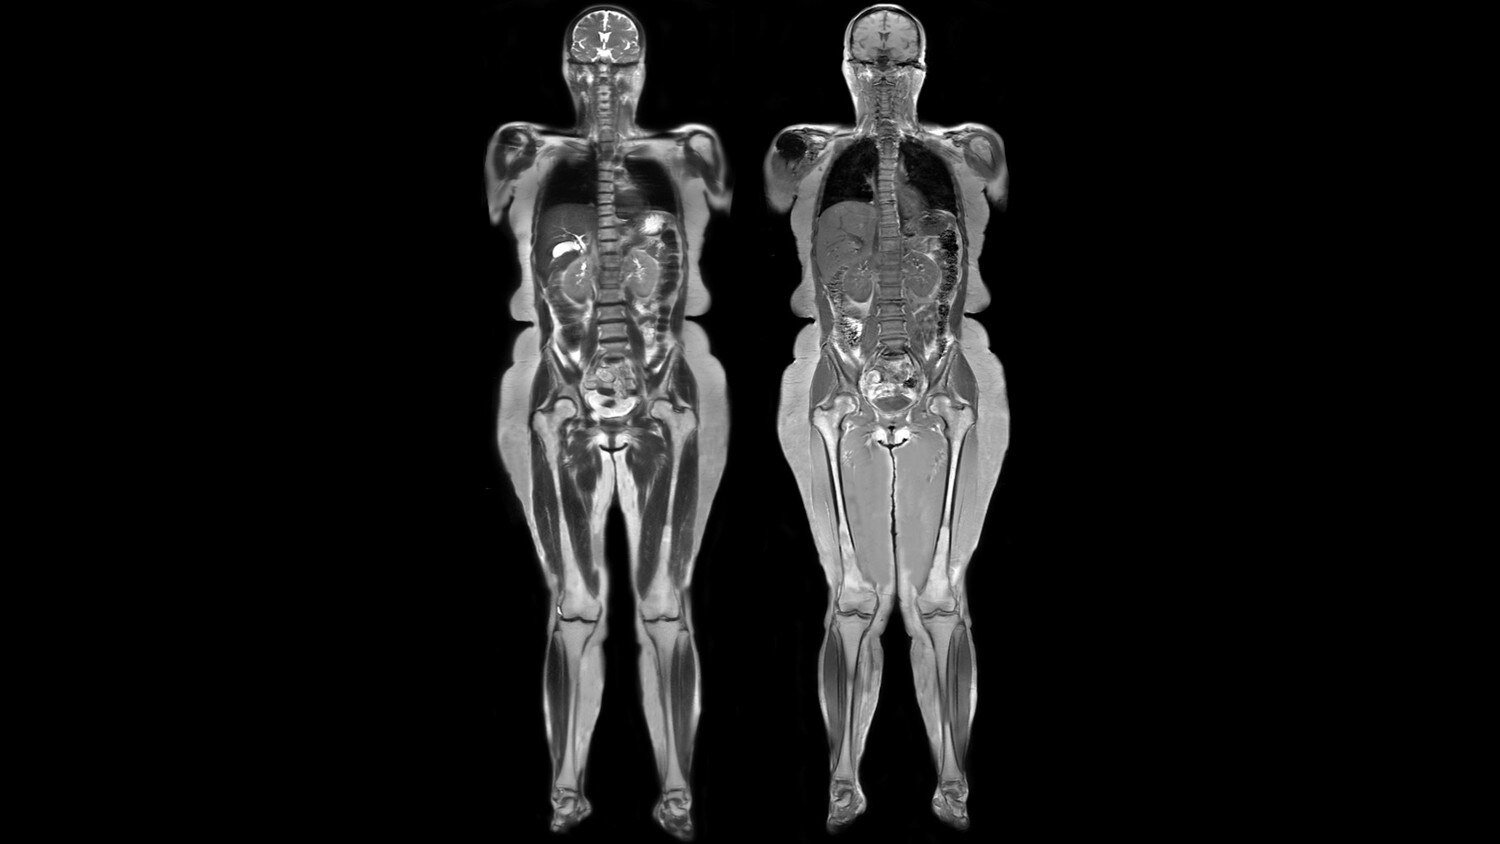

A new, leading-edge MR system combining a 70 cm patient bore with 3.0T magnet strength.

We've integrated the power of 3.0T with a 70 cm wide bore that patients deserve. And that's just the beginning.

Its full 3.0T magnet and 70 cm bore work together to generate extraordinary image quality without compromises. The result for clinicians is new levels of diagnostic performance.

Magnet A new, light-weight magnet with a compact footprint that supports a 70 cm patient gantry and offers a large 50 x 50 x 50 cm useable field of view with excellent homogeneity for uncompromised coverage and quality.

A large usable field of view is needed to properly image off-center anatomy such as a shoulder or hip. So the Discovery* MR750w features a 70 cm flared, open bore design with a large 50 x 50 x 50 cm field of view.

Key features include feet-first imaging for all anatomies, flexible designs that comfortably embrace the patient, comfort tilt to improve brain and neck exam form, reduced exam times through fewer coil exchanges, and comfortable variable density padding designed to help minimize pressure points. Each component of the GEM Suite can be used individually or combined for complete head-to-toe imaging.